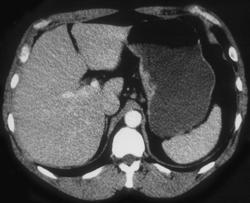

Gastric Banding Procedure With Inflatable Band